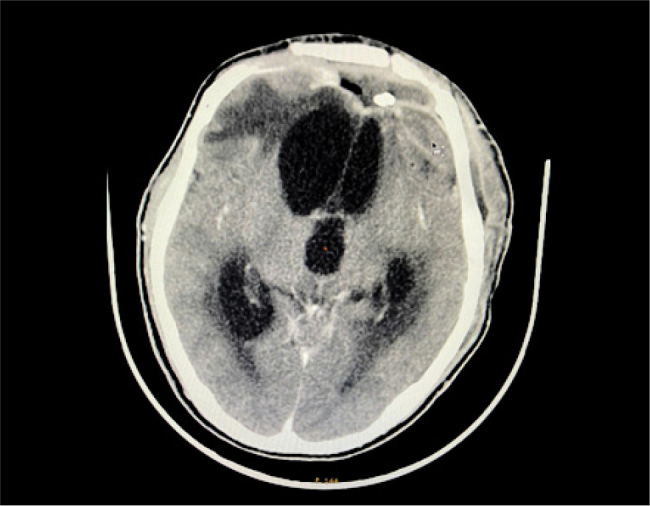

Case description: We present two cases of brain abscess treated at a tertiary care centre using continuous abscess cavity irrigation after conventional interventions proved insufficient. The first patient, a 15-year-old male, experienced recurrent MDR brain abscesses despite multiple surgical procedures and broad-spectrum antibiotics. Initiation of continuous irrigation, combined with targeted antimicrobial therapy, resulted in rapid clinical stabilisation and marked radiological improvement, with minimal long-term sequelae. The second patient, a 65-year-old female, developed multiple brain abscesses after traumatic brain injury and decompressive surgery. Although continuous irrigation effectively controlled the intracranial infection and imaging confirmed resolution, her neurological recovery was limited due to profound pre-existing brain damage.